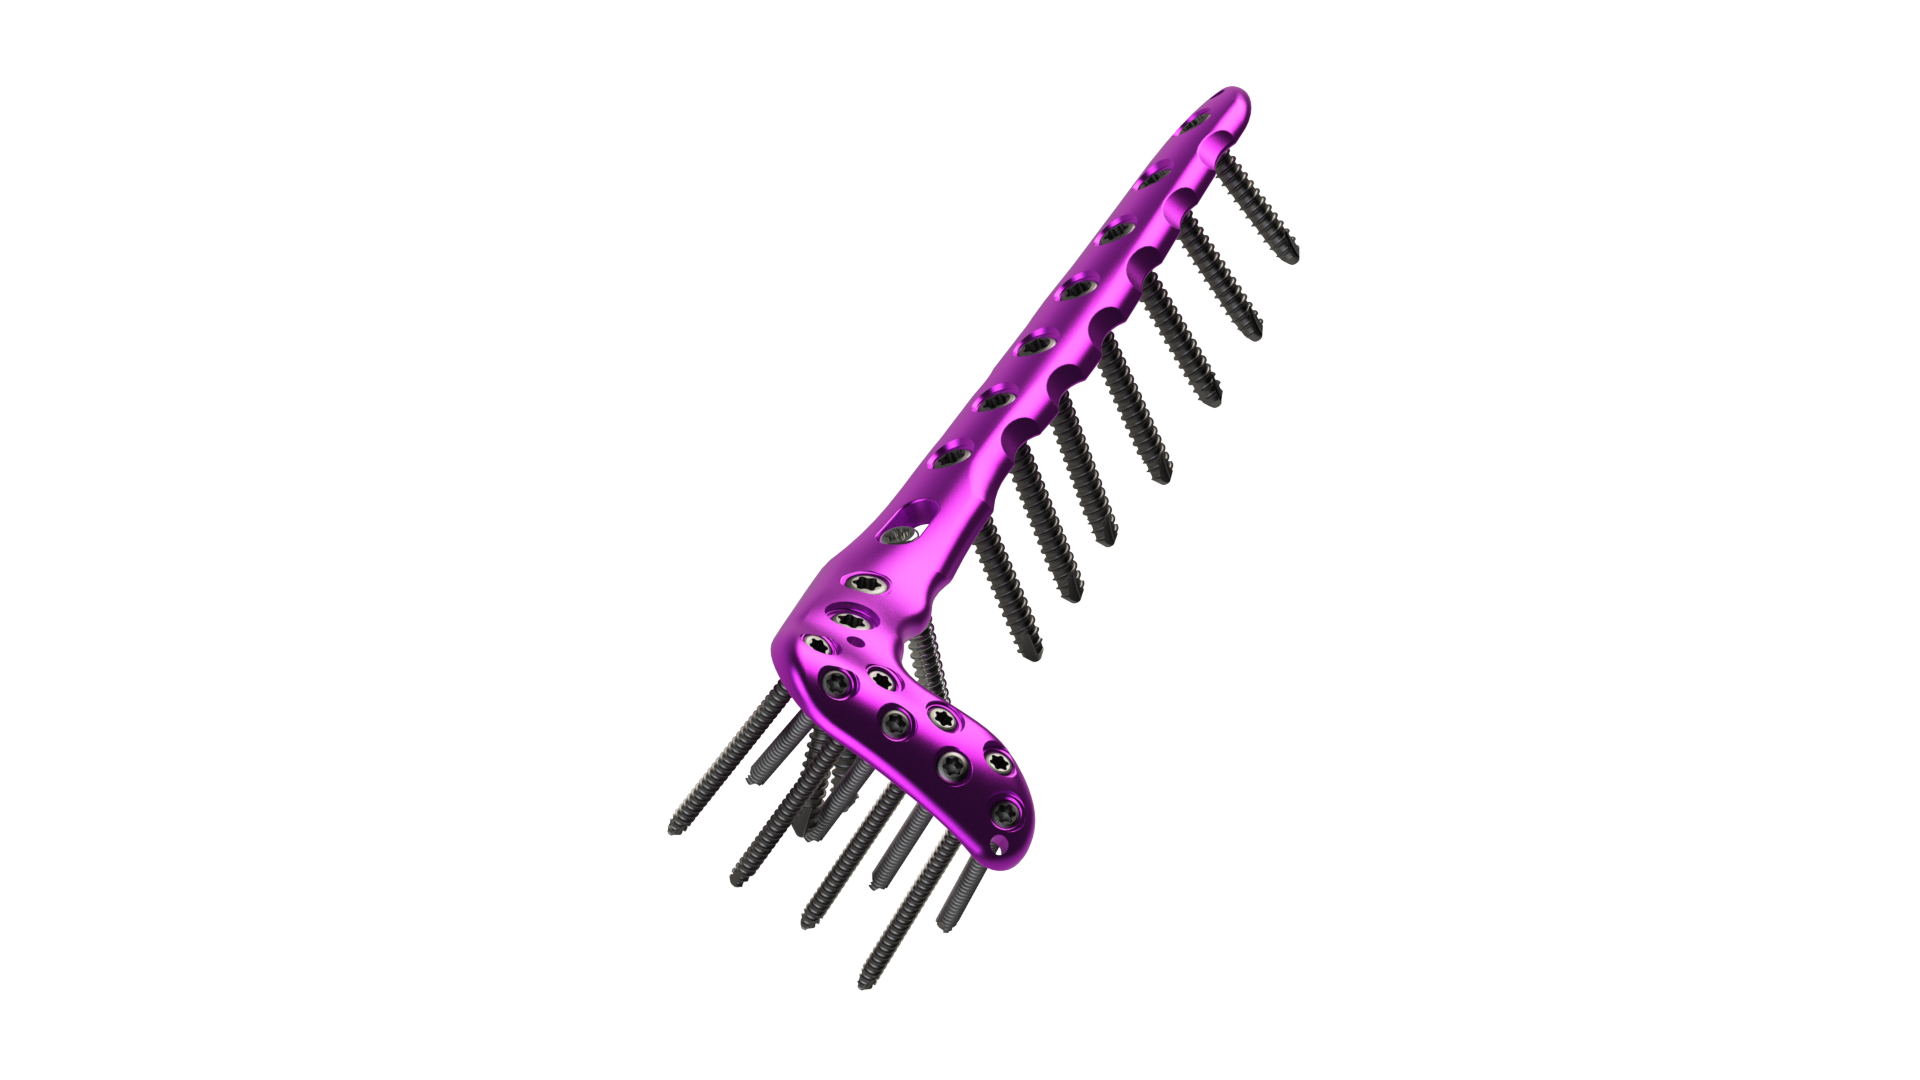

Proximal Tibia

Plates and Screws

Distal Tibia

Plates and Screws